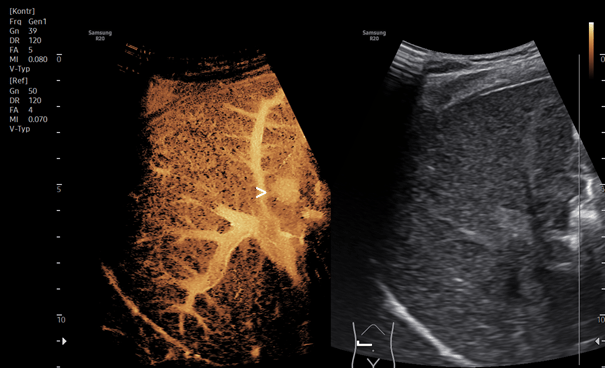

The detailed analysis utilized the new high-resolution, color-coded contrast ultrasound technique in Super Resolution mode, MV-CEUS. The false-color analysis with rapid, high contrast from the center to the periphery facilitated the localization of small focal lesions in the right liver lobe (Fig.2).